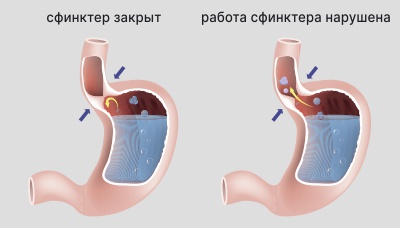

Чтобы такого не происходило, в организме предусмотрены специальные клапаны — сфинктеры. Так, клапан, расположенный в нижнем отделе пищевода, не даёт содержимому желудка попасть в пищевод.

Рефлюкс — это состояние, при котором клапан не работает как следует и кислота из желудка забрасывается в пищевод, провоцируя ожог и воспаление

Рефлюкс-эзофагит — воспаление пищевода, вызванное забросом в него кислого содержимого желудка.

Основная причина развития рефлюкс-эзофагита у детей — недостаточно развитый нижний отдел пищевода. У взрослых — проблемы с работой сфинктера в нижнем отделе пищевода.

У детей рефлюкс-эзофагит может возникнуть из-за недостаточно развитого нижнего отдела пищевода. Клапан (сфинктер) в нижнем отделе у детей не всегда срабатывает как нужно, в результате содержимое желудка попадает в пищевод.

У взрослых рефлюкс-эзофагит может развиться из-за повышенного давления на сфинктер нижнего отдела пищевода, недостаточной работы сфинктера — когда эта естественная заслонка не справляется и пропускает желудочное содержимое в пищевод, а также из-за повышенной кислотности желудочного сока — при этом даже единичные забросы желудочного содержимого разрушительно действуют на пищевод.